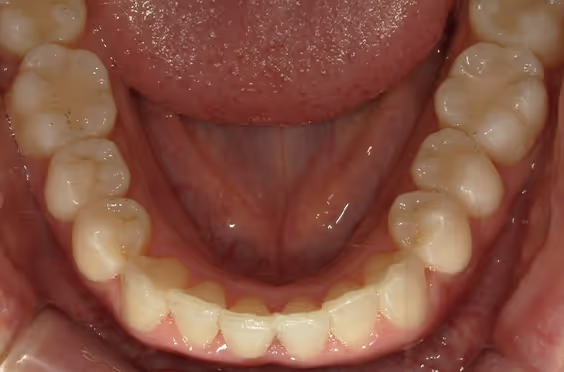

- 症例1

治療期間 4カ月

治療費 23.1万円(月額1,925円~)

※上顎前歯部、下顎前歯部の叢生をマウスピース型矯正装置で改善したケース。矯正治療上のリスクとして、治療中の虫歯、歯根吸収、歯肉炎 ・歯周炎の発生などが考えられる。